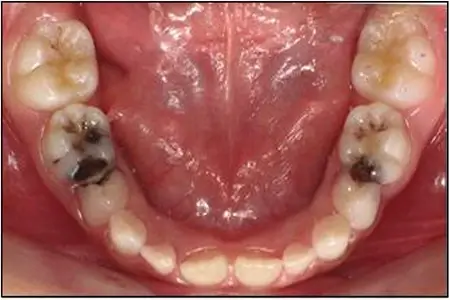

कैविटी (दांत में छेद)

कैविटी को क्षरण या दांतों की सड़न भी कहा जाता है। ये दांत के ऐसे क्षेत्र होते हैं, जो स्थायी रूप से क्षतिग्रस्त हो गए हैं और उनमें छेद भी हो सकते हैं। कैविटी काफी आम है। वे तब होते हैं, जब बैक्टीरिया भोजन और एसिड की परत आपके दांतों पर चढ़ा देते हैं और प्लाक बनाते हैं।

आपके दांतों पर मौजूद एसिड इनेमल और फिर दांत की भीतरी कठोर परत या संयोजी ऊतक को खत्म करना शुरू कर देता है। समय के साथ, यह स्थायी क्षति का कारण बन सकता है।